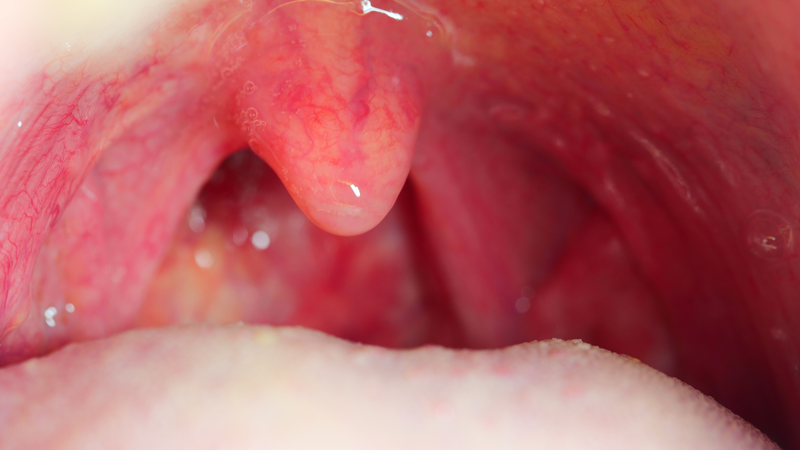

Cắt amidan là một trong những phương pháp điều trị được áp dụng khi viêm amidan ở người lớn trở nên nghiêm trọng hoặc tái phát liên tục. Tuy nhiên, không phải trường hợp nào cũng cần phẫu thuật. Vậy có nên cắt amidan cho người lớn không? Hiểu rõ lợi ích và rủi ro của việc cắt amidan sẽ giúp người bệnh tự tin hơn trong việc đưa ra quyết định phù hợp với bản thân.

Viêm amidan là tình trạng khá phổ biến ở người lớn, gây ra các triệu chứng khó chịu như đau họng, nuốt vướng, sốt và hơi thở có mùi. Khi bệnh tái phát nhiều lần hoặc kéo dài dai dẳng, nhiều người băn khoăn không biết có nên cắt amidan hay không.